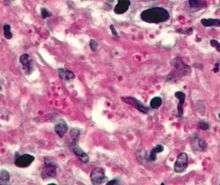

Ziehl-Neelsen stain

Ziehl-Neelsen staining is used to stain species of Mycobacterium tuberculosis that do not stain with the standard laboratory staining procedures such as Gram staining.

The stains used are the red coloured Carbol fuchsin that stains the bacteria and a counter stain such as Methylene blue